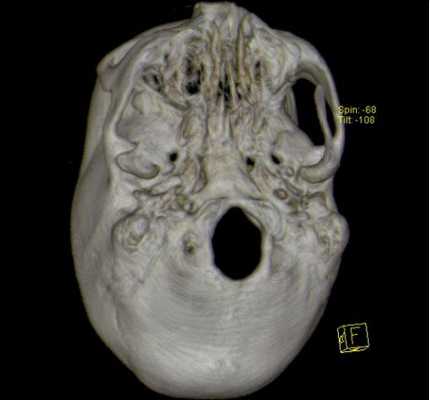

3D-реконструкция с помощью компьютерной томографии

Показанием для проведения КТ основания черепа могут служить следующие жалобы больного: